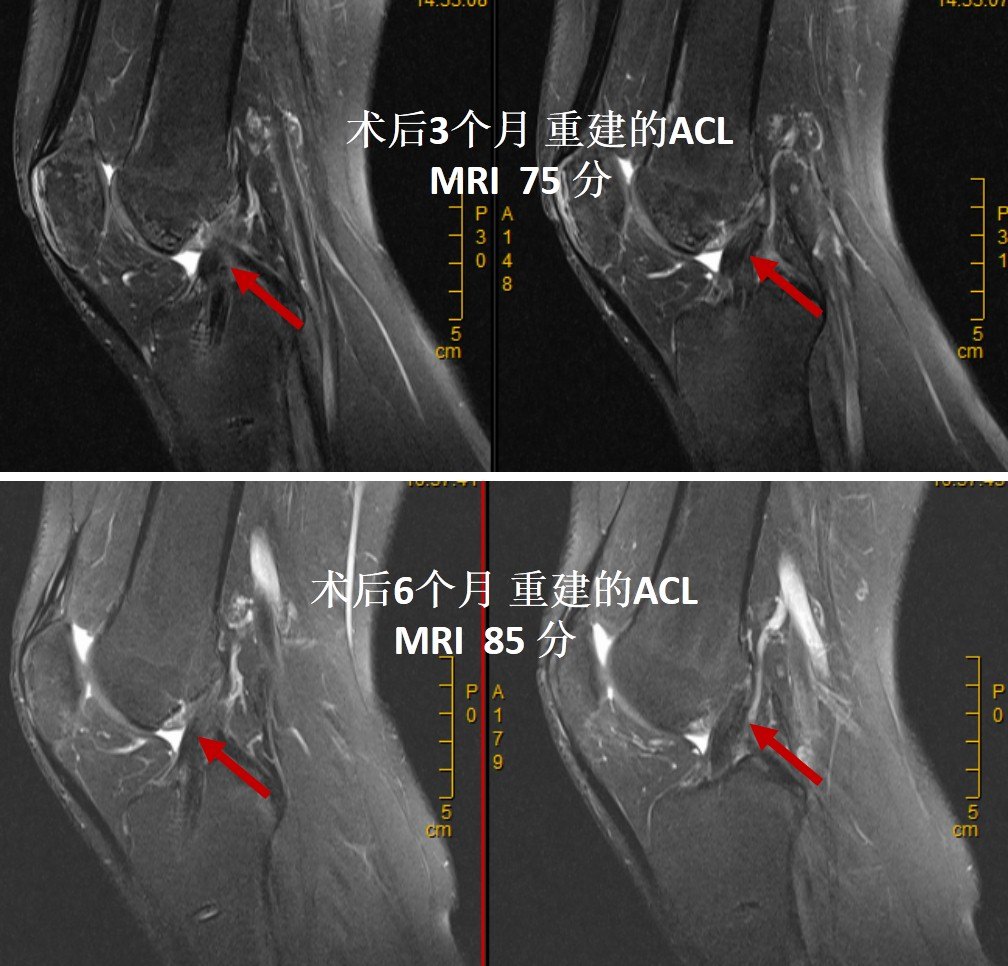

Author rihaworks70 Created Date AMACL再建術後のランニング開始時の膝伸展筋力,筋力 基準は種々報告されており,Paessler4)は術後3か月での 膝伸展筋力患健比が65%,櫻井,清水は等尺性膝伸展筋 力患健比が60~70%5)~6)としている.また,ランニンAclの再建を行った患者のうち、リハビリテーション経過を 観察できた18名(男性8名、女性10名)を対象とした mriを 用いて術後3、 4、 6、 9、 12ケ月経過時に大腿部の筋体積を 計測した。 acl再建術後の大腿四頭筋では内側広筋を中心とし